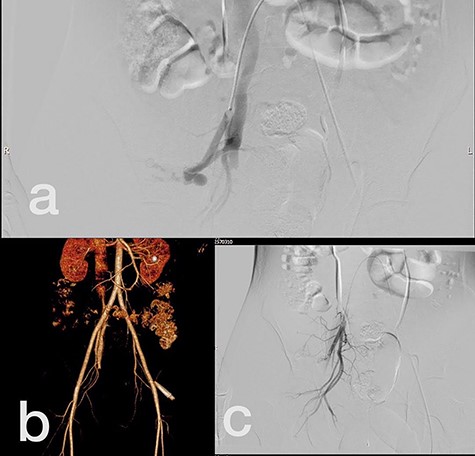

Sites of injury included 6 Posterior Tibialis arteries (27.2%) (Fig. 1), 2 deep femoral arteries (9.09%), 2 Superficial femoral arteries (9.09%) and 2 maxillary arteries (9.09%). We had only one injured artery (4.54%) in each of the following sites: internal pudendal a., Axillary a. (Fig. 2), Proneal a., Lumbar a., External carotid a., Anterior Tibialis a., common iliac a. (Fig. 3), temporal a., Thoracic aorta and Internal iliac artery (Fig. 4).

(a) Common iliac artery before intervention, (b) after stent-graft deployment.